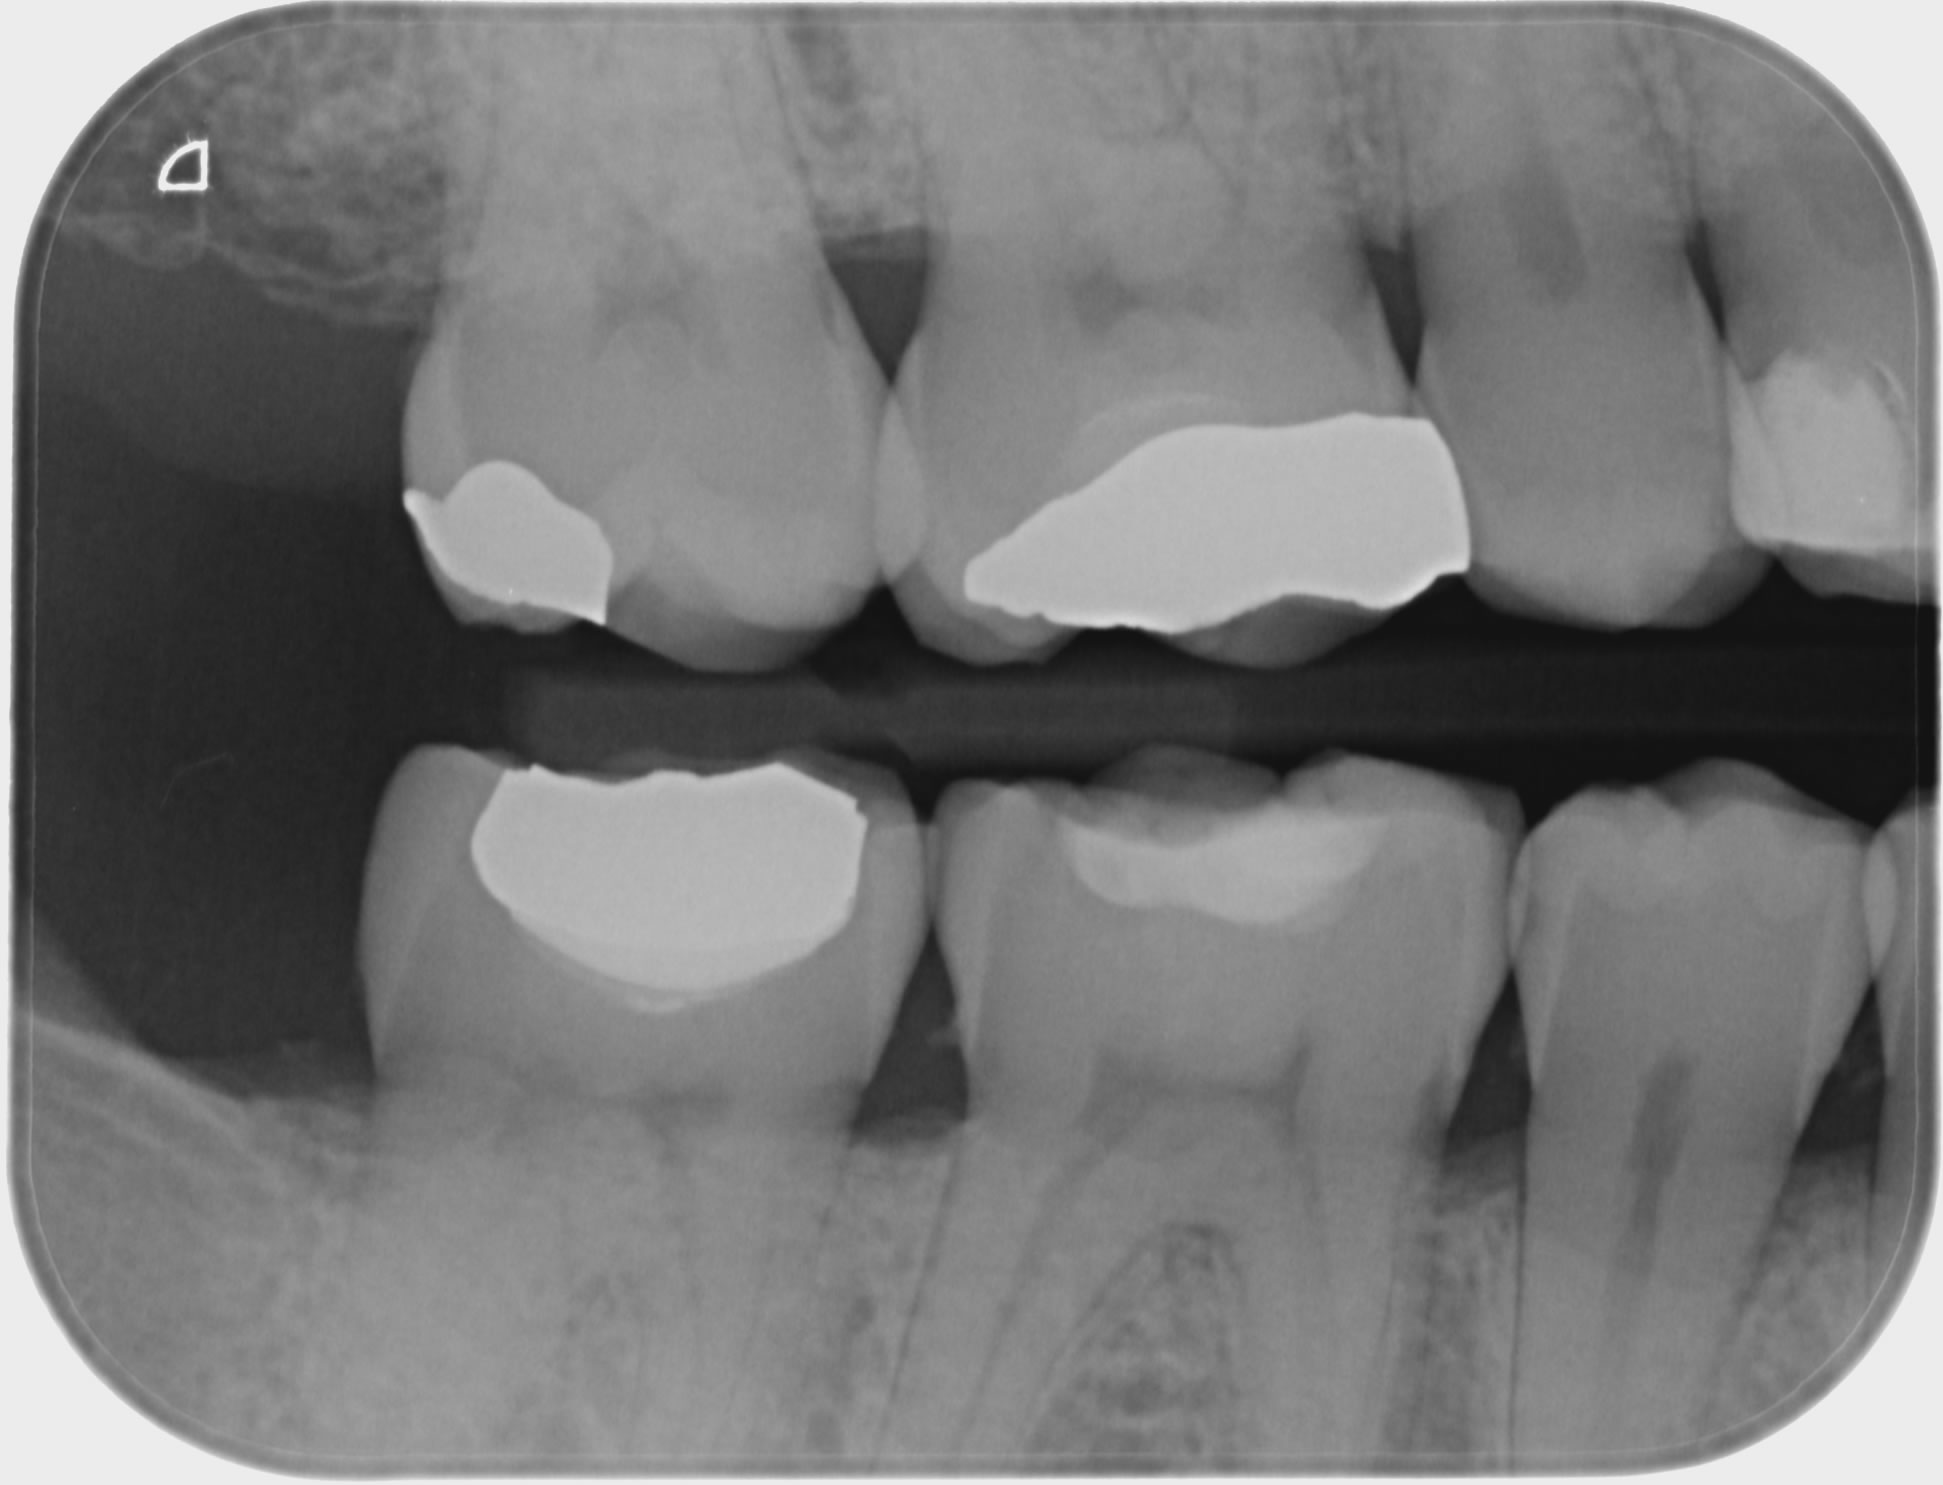

What Is A Bitewing X Ray . the bitewing radiograph (bw) is an image that depicts the maxillary and mandibular crowns of the teeth, providing a clear. Bitewings reveal the presence and extent of decay in the back teeth, specifically in.

Bitewings reveal the presence and extent of decay in the back teeth, specifically in. the bitewing radiograph (bw) is an image that depicts the maxillary and mandibular crowns of the teeth, providing a clear.